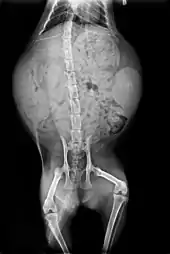

Skeleton

Cats have seven cervical vertebrae (as do most mammals); 13 thoracic vertebrae (humans have 12); seven lumbar vertebrae (humans have five); three sacral vertebrae (as do most mammals, but humans have five); and a variable number of caudal vertebrae in the tail (humans have only three to five vestigial caudal vertebrae, fused into an internal coccyx).[49]: 11 The extra lumbar and thoracic vertebrae account for the cat's spinal mobility and flexibility. Attached to the spine are 13 ribs, the shoulder, and the pelvis.[49]: 16 Unlike human arms, cat forelimbs are attached to the shoulder by free-floating clavicle bones which allow them to pass their body through any space into which they can fit their head.[50]